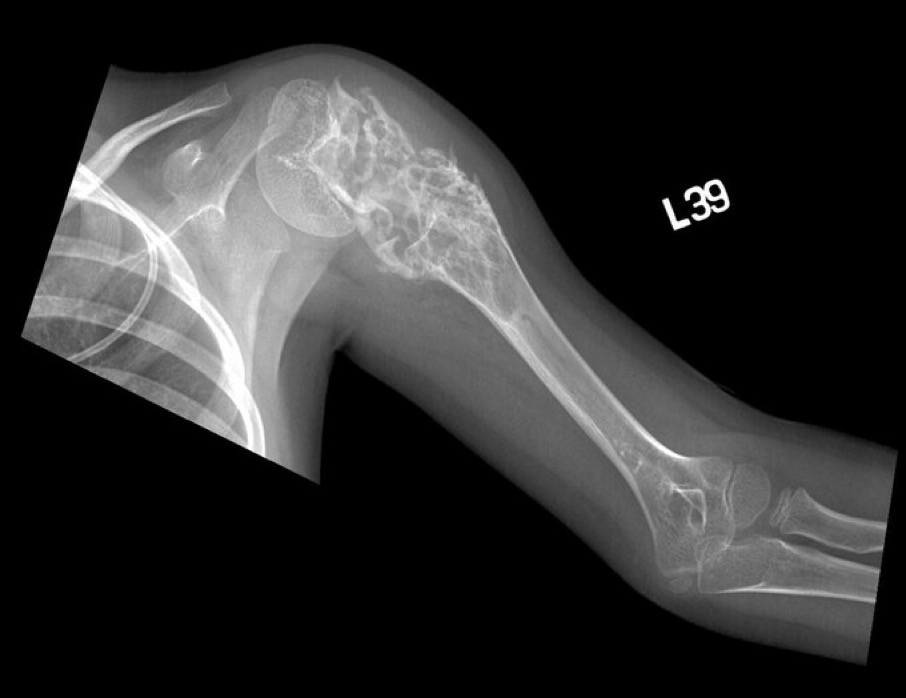

Swollen shoulder, Xray Stock Image C048/2964 Science Photo Library Top Of Left Shoulder Swollen Sometimes, excessive use of the shoulder leads to inflammation and swelling of the bursa between the rotator cuff and part of the shoulder blade known as the acromion. Ask for an urgent gp appointment or get help from nhs 111 if: We look at symptoms, causes, and ways of relieving the pain. Don’t ignore obvious warning signs of more serious. Top Of Left Shoulder Swollen.